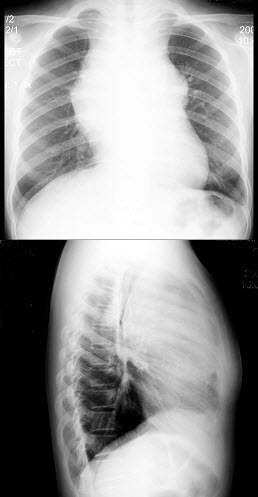

52、单项选择题

男,52岁,胸痛、体重下降2月余,结合胸片,最可能的诊断()

A.包裹性胸腔积液

B.胸膜肥厚

C.化脓性胸膜炎

D.肺癌

E.胸膜间皮瘤

点击查看答案